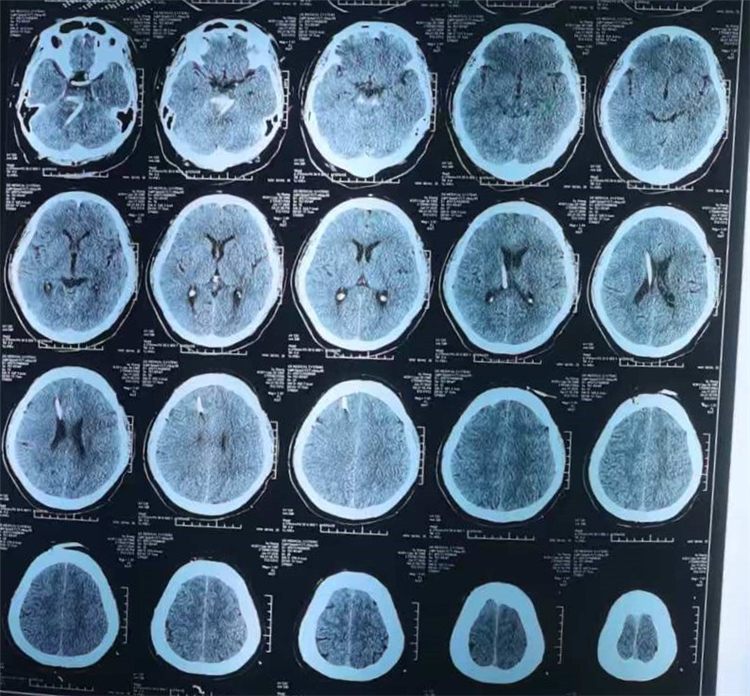

术后复查CT:脑干血肿全部清除

医院立即启动卒中救治绿色通道。神经外科团队迅速评估病情,制定周密手术方案。脑干区域手术素有“生命禁区”之称,手术风险极高,任何损伤都可能造成不可逆的后果。在取得家属知情同意后,神经外科联合麻醉科、放射科等多学科协作,为患者实施“立体定向颅内血肿穿刺引流术+脑室钻孔引流术”。手术过程顺利,术后患者逐渐恢复意识,右侧肢体可遵嘱活动,病情趋于平稳。

经过系统治疗与精心护理,吴先生目前已康复出院。该病例的成功救治,不仅得益于患者自身的顽强意志与家属的支持,也体现了医院多学科协作的优势与神经外科团队的技术实力。